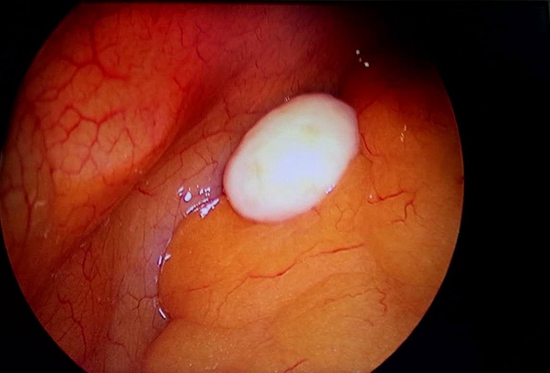

近日,我院外科在对一位患者施行经腹腔镜行阑尾切除术时,发现该患者腹腔内有一个白色的“蛋”。

术中,在腹腔镜下,医生清晰地看见“蛋”成椭圆形,在腹腔内可以自由滚动,腹腔镜钳夹之不能破裂,具有一定的韧性,取出后大小约1.5cm×2cm,与腹腔任何组织无粘连,表面光滑,手触质地稍软,有弹性。

据外科主任陈元怀介绍,这个蛋形的物体是肠脂垂,主要是沿结肠带两侧分布的,由浆膜及其所包含的脂肪组织构成的许多小突起状物,由于缺血和坏死脱落后,依靠腹腔内液体营养包裹生长而形成的腹腔游离体,所以看起来像是一个蛋,会随着人体体位变化而滚动。该病发病率很低,在我院也是首例,一般情况下对患者的工作和生活不产生影响,但不断长大就会压迫膀胱或肠管,产生尿频或肠梗阻症状,或继发肠脂垂炎,所以一旦发现应及时取出,防止变性。